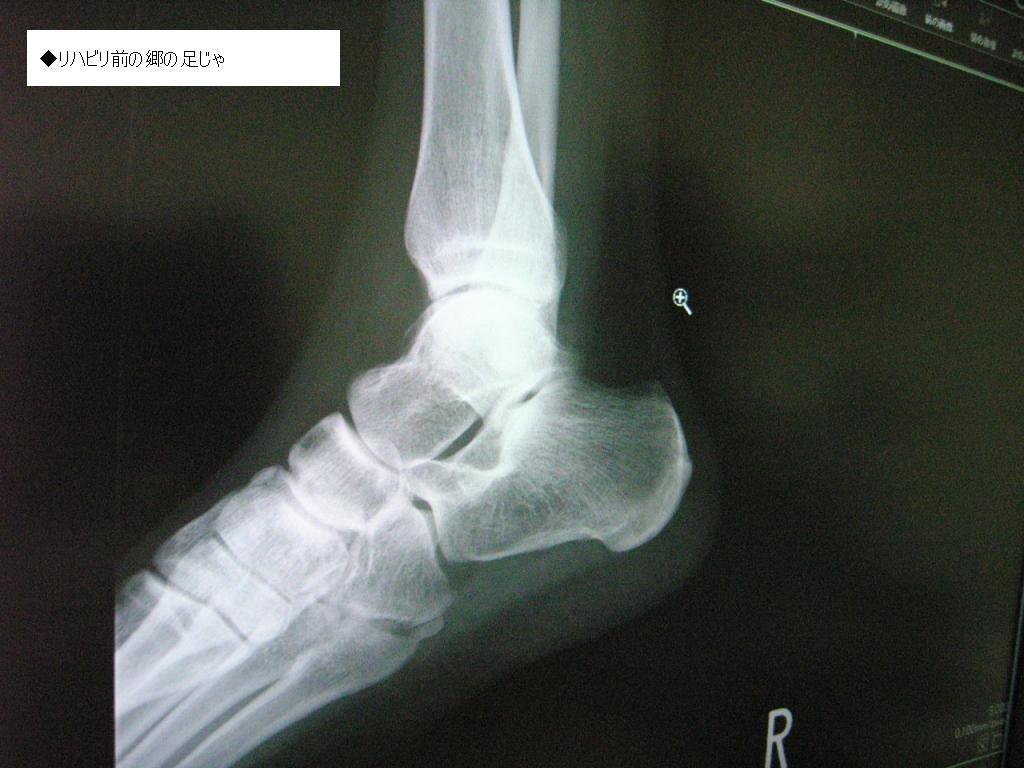

◆無くなった郷の軟骨っ♪

レントゲンを速攻で撮影し、再び診断室へ郷w

先生様『骨が・・・無くなってる。以前骨折ったことある?』

先生様『ほらここ、右足首クルブシの下スッポリ溶けてるね』

ショックに追い討ちをかけるように、足首の左右にある間接の隙間が殆んど無い状態であることを告げられる。